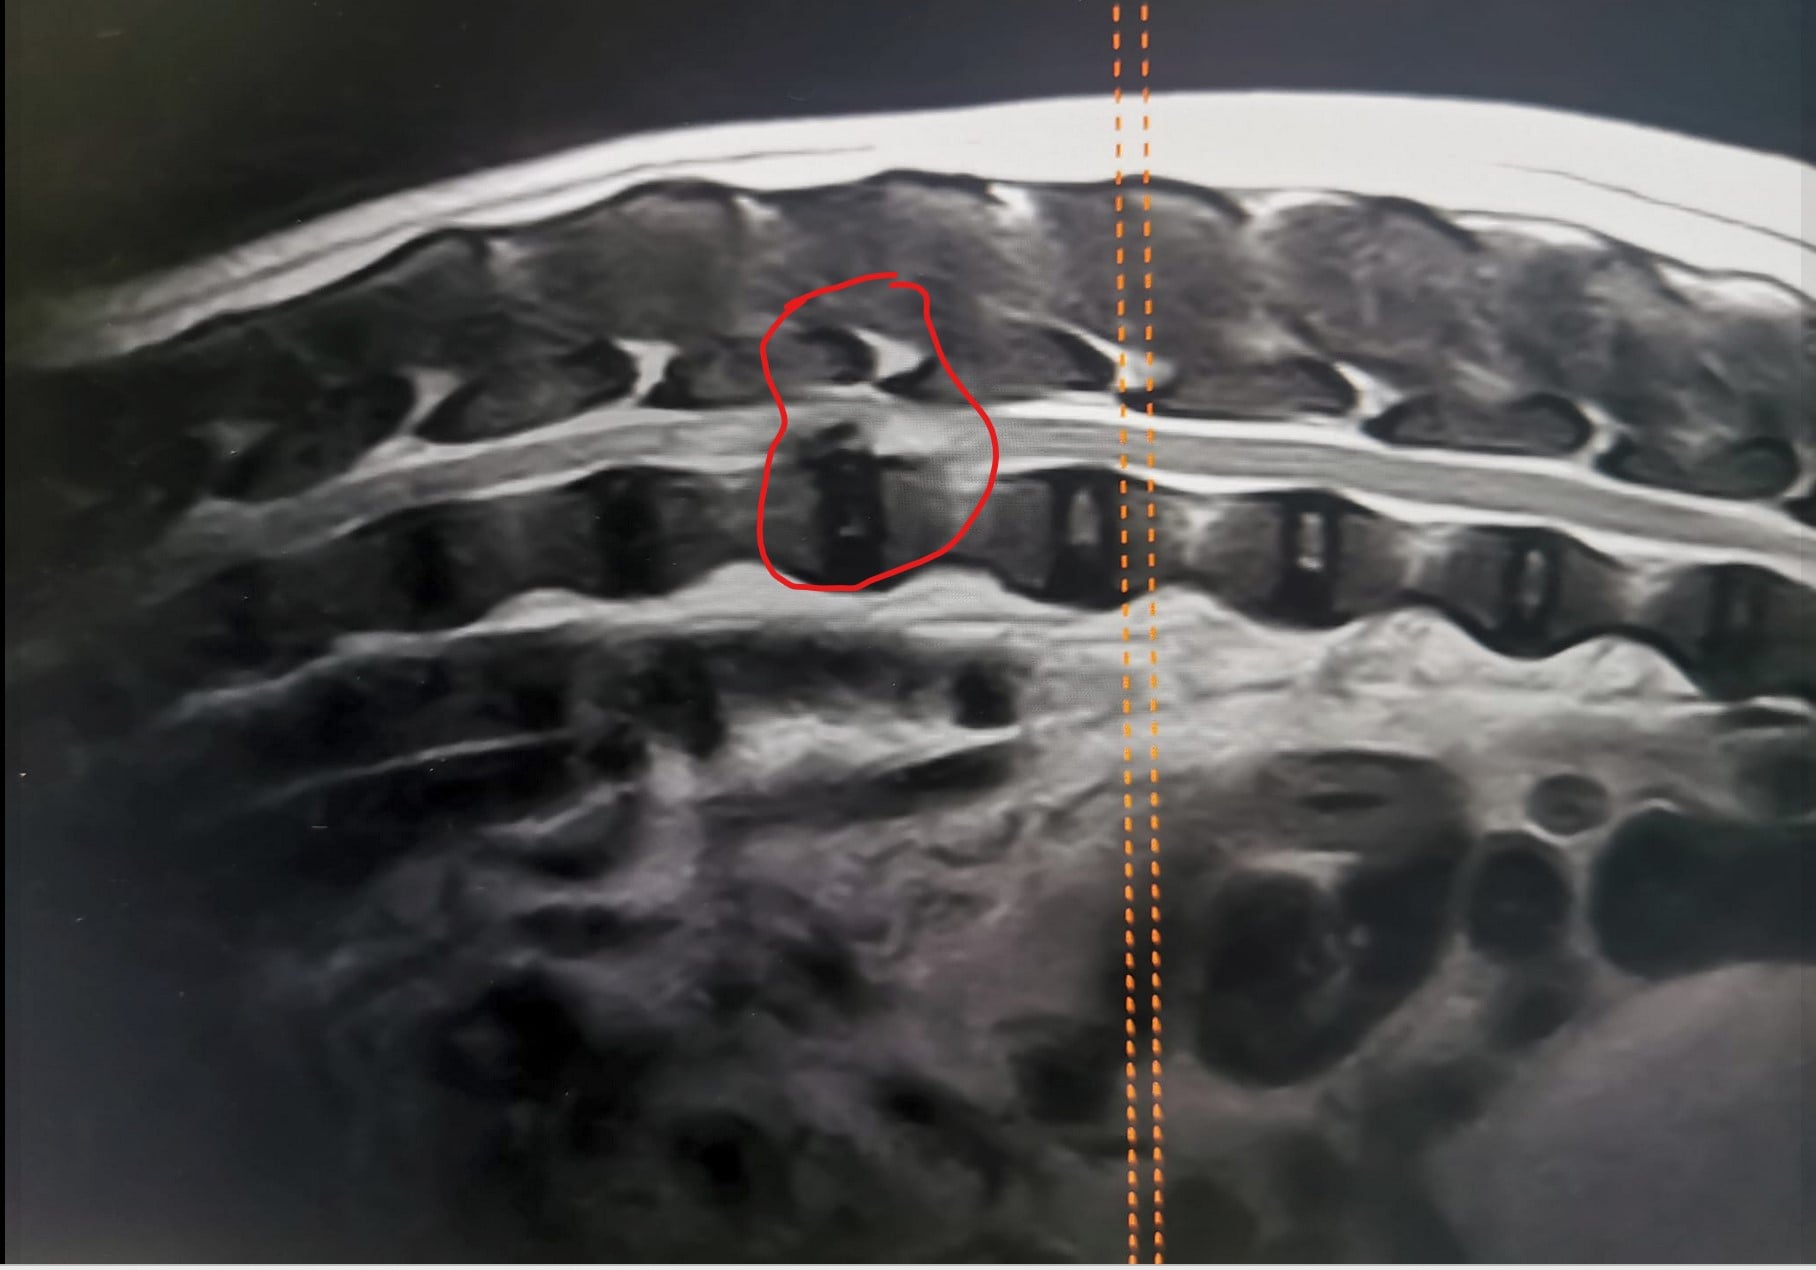

Kyynärnivelen epäyhdenmukaisuus näkyy parhaiten röntgenkuvassa, jossa niveltä ei ole taivutettu (avautumiskulma 90 astetta tai enemmän). Röntgenkuvassa täytyy näkyä kyynärnivelen lisäksi koko kyynärvarsi. Epäyhdenmukaisuus (inkongruenssi) arvioidaan asteikolla INC0–INC3, jossa INC0 on yhdenmukainen ja INC3 voimakkaasti epäyhdenmukainen nivel. Kondrodystrofisilla roduilla INC1 on vielä "normaali", mutta INC2- ja INC3-kyynärnivelet ovat selvästi epänormaaleja.